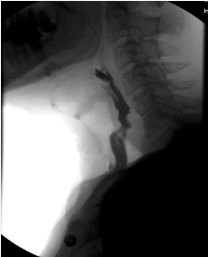

A 52-year-old male presented with a TEF more than 1.5 years following hospitalization for a severe COVID-19 infection. During this time, he required intubation and IMV for 69 days due to ARDS. His hospital course was complicated by two cardiac arrests, stroke, acute kidney injury requiring dialysis, osteomyelitis of the cervical spine, and sacral decubitus ulcers requiring colostomy diversion. Tracheostomy was performed and the patient was ultimately weaned from IMV. He made a significant recovery, but subsequently developed poor oral intake, chronic vomiting, and weight loss of 113 pounds. The patient was unable to swallow saliva and was completely dependent on his gastrostomy tube for nutrition. A modified barium swallow demonstrated a TEF with complete PES (Figure 2).

Figure 2 Modified barium swallow showing tracheoesophageal fistula with complete pharyngoesophageal stenosis and demonstrating aspiration of the entire bolus.

Figure 2: Modified barium swallow showing tracheoesophageal fistula with complete pharyngoesophageal stenosis and demonstrating aspiration of the entire bolus.